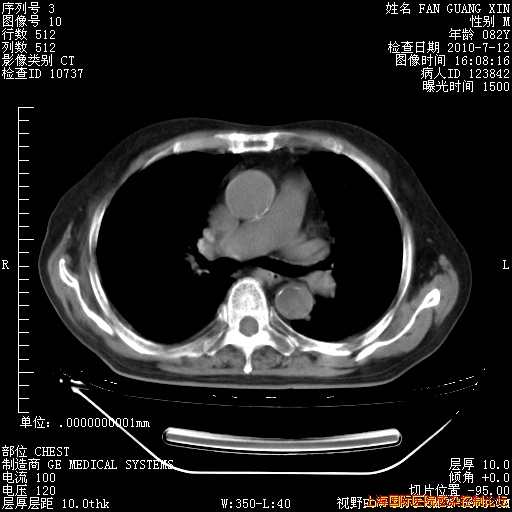

今天复查CT

今天CT

整整相隔30天的肺部CT好像有所好转啊。甲强龙减量第3天,需要观察体温。